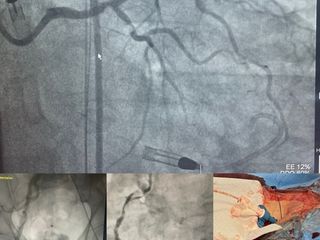

All’ospedale di Savigliano è stato portato a termine con successo un delicato intervento di rivascolarizzazione percutanea complessa con il supporto dell’Impella, un dispositivo avanzato per l’assistenza ventricolare sinistra, ovvero una pompa che viene inserita nel cuore del paziente passando tramite un’arteria femorale per garantire la circolazione ottimale del sangue anche in caso di insufficienza cardiaca.

L’intervento è stato eseguito dall’équipe composta dal direttore della struttura di Cardiologia Michele De Benedictis, con i colleghi Umberto Barbero e Mattia Doronzo recentemente entrato a far parte della struttura, e riguardava un paziente con multiple gravi stenosi coronariche e con il cuore affetto da una grave riduzione della capacità di pompare il sangue.

“Il supporto dell’Impella ci ha permesso di affrontare una situazione estremamente complessa in totale sicurezza, sostenendo la funzione cardiaca durante tutto l’intervento” spiega il dottor Barbero. Che aggiunge: “Abbiamo inoltre utilizzato un’innovativa tecnica di impianto perfezionata per ridurre al minimo l’invasivitá della puntura femorale che ha garantito al paziente sicurezza durante la procedura e tempi di recupero rapidissimi”.